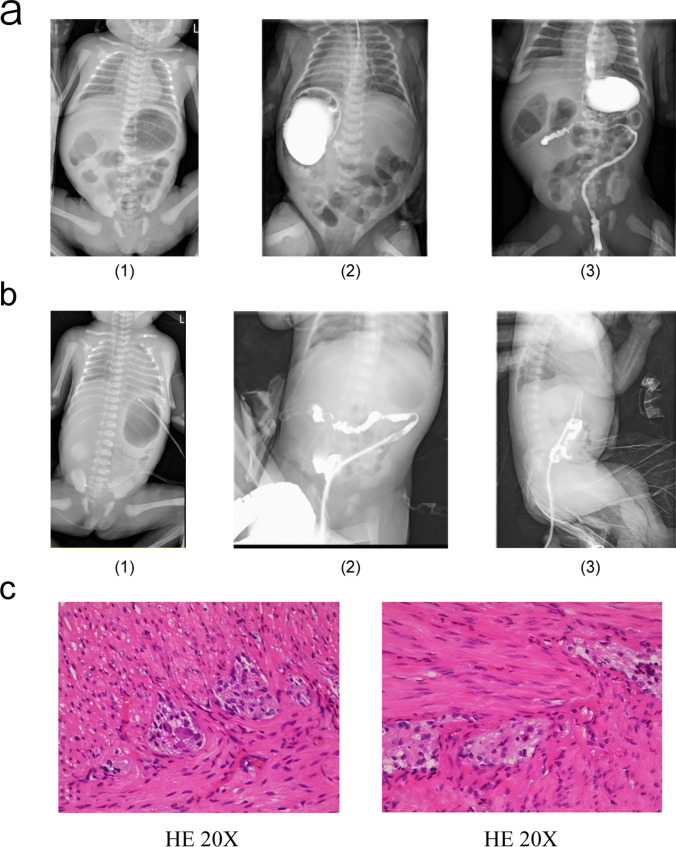

Gastrointestinal Defects and Immunodeficiency Syndrome-1 (GIDID-1), caused by abnormalities in TTC7A, is an autosomal recessive disorder characterized by multiple gastrointestinal malformations and immune deficiencies, often accompanied by inflammatory bowel disease (IBD). This condition typically results in poor treatment outcomes and is usually fatal in early infancy. This paper examined the genetic abnormalities and clinical features of GIDID by analyzing data from three children and one fetus with gastrointestinal dysfunction and immune deficiency associated with TTC7A abnormalities at our hospital, and reviewed reported cases worldwide. Genetic analysis of the four patients identified eight novel variants in the TTC7A, five of which were likely pathogenic variants, while three were of uncertain significance. Including the cases reported in this paper and through a literature review, there were 89 known cases globally, involving 79 TTC7A variants. Patients typically presented with multiple gastrointestinal malformations, immune deficiencies, or IBD. Thus, genetic testing is recommended for patients with multiple gastrointestinal malformations and recurrent infections to determine if GIDID is due to TTC7A abnormalities. The syndrome generally has a poor prognosis, and this information is crucial for treatment planning, prenatal screening, and genetic counseling.